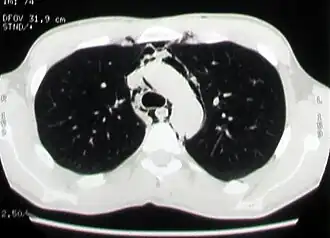

Основными методами диагностики спонтанного пневмомедиастинума являются рентгенография грудной клетки в прямой и боковых проекциях и компьютерная томография органов грудной клетки. Другие инструментальные исследования, такие как рентгеноконтрастное исследование пищевода, фиброэзофагогастродуоденоскопия, фибротрахеобронхоскопия, электрокардиография, назначаются с целью исключения другой патологии, имеющей сходные клинические или рентгенологические проявления[1][8][22].

На рентгенограммах обнаруживаются полосы просветления или пузырьки газа, окружающие тень средостения, приподнимая медиастинальную плевру, довольно часто описанные изменения распространяются на шею и грудную стенку. При рентгенографии в прямой проекции свободный газ в средостении часто обнаруживается по левой границе сердца и покрывает внутреннюю поверхность медиастинальной плевры, при этом создаётся хорошо заметная плевральная линия кнаружи от легочного ствола и дуги аорты. На боковых рентгенограммах свободный газ обуславливает полосы просветления вдоль контуров восходящей аорты, дуги аорты и отходящих от неё ветвей, легочных артерий и трахеи. Свободный газ располагается и вдоль линии прикрепления диафрагмы к грудине, вдоль тимуса и плече-головных вен[2][6][27][28].

В ряде случаев диагностировать пневмомедиастинум при обзорной рентгенографии затруднительно ввиду наличия у пациентов выраженной эмфиземы мягких тканей грудной клетки, экранирующей средостение. В таких случаях целесообразно выполнение компьютерной томографии органов грудной клетки[2][19].

Компьютерная томография органов грудной клетки

Компьютерная томография является наиболее эффективным методом диагностики эмфиземы средостения, так как с его помощью легко выявляется наличие газа в средостении, на поперечных сечениях хорошо определяется его локализация и распространённость эмфиземы. Преимуществом перед рентгенографией является возможность диагностики пневмомедиастинума даже в тех случаях, когда имеется выраженная эмфизема мягких тканей грудной стенки, сводящая информативность рентгенографии в этой ситуации к минимуму. Кроме того, компьютерная томография позволяет провести дифференциальную диагностику спонтанного пневмомедиастинума и других заболеваний с похожей клинической картиной, а также важна для установления причины заболевания[2][21].